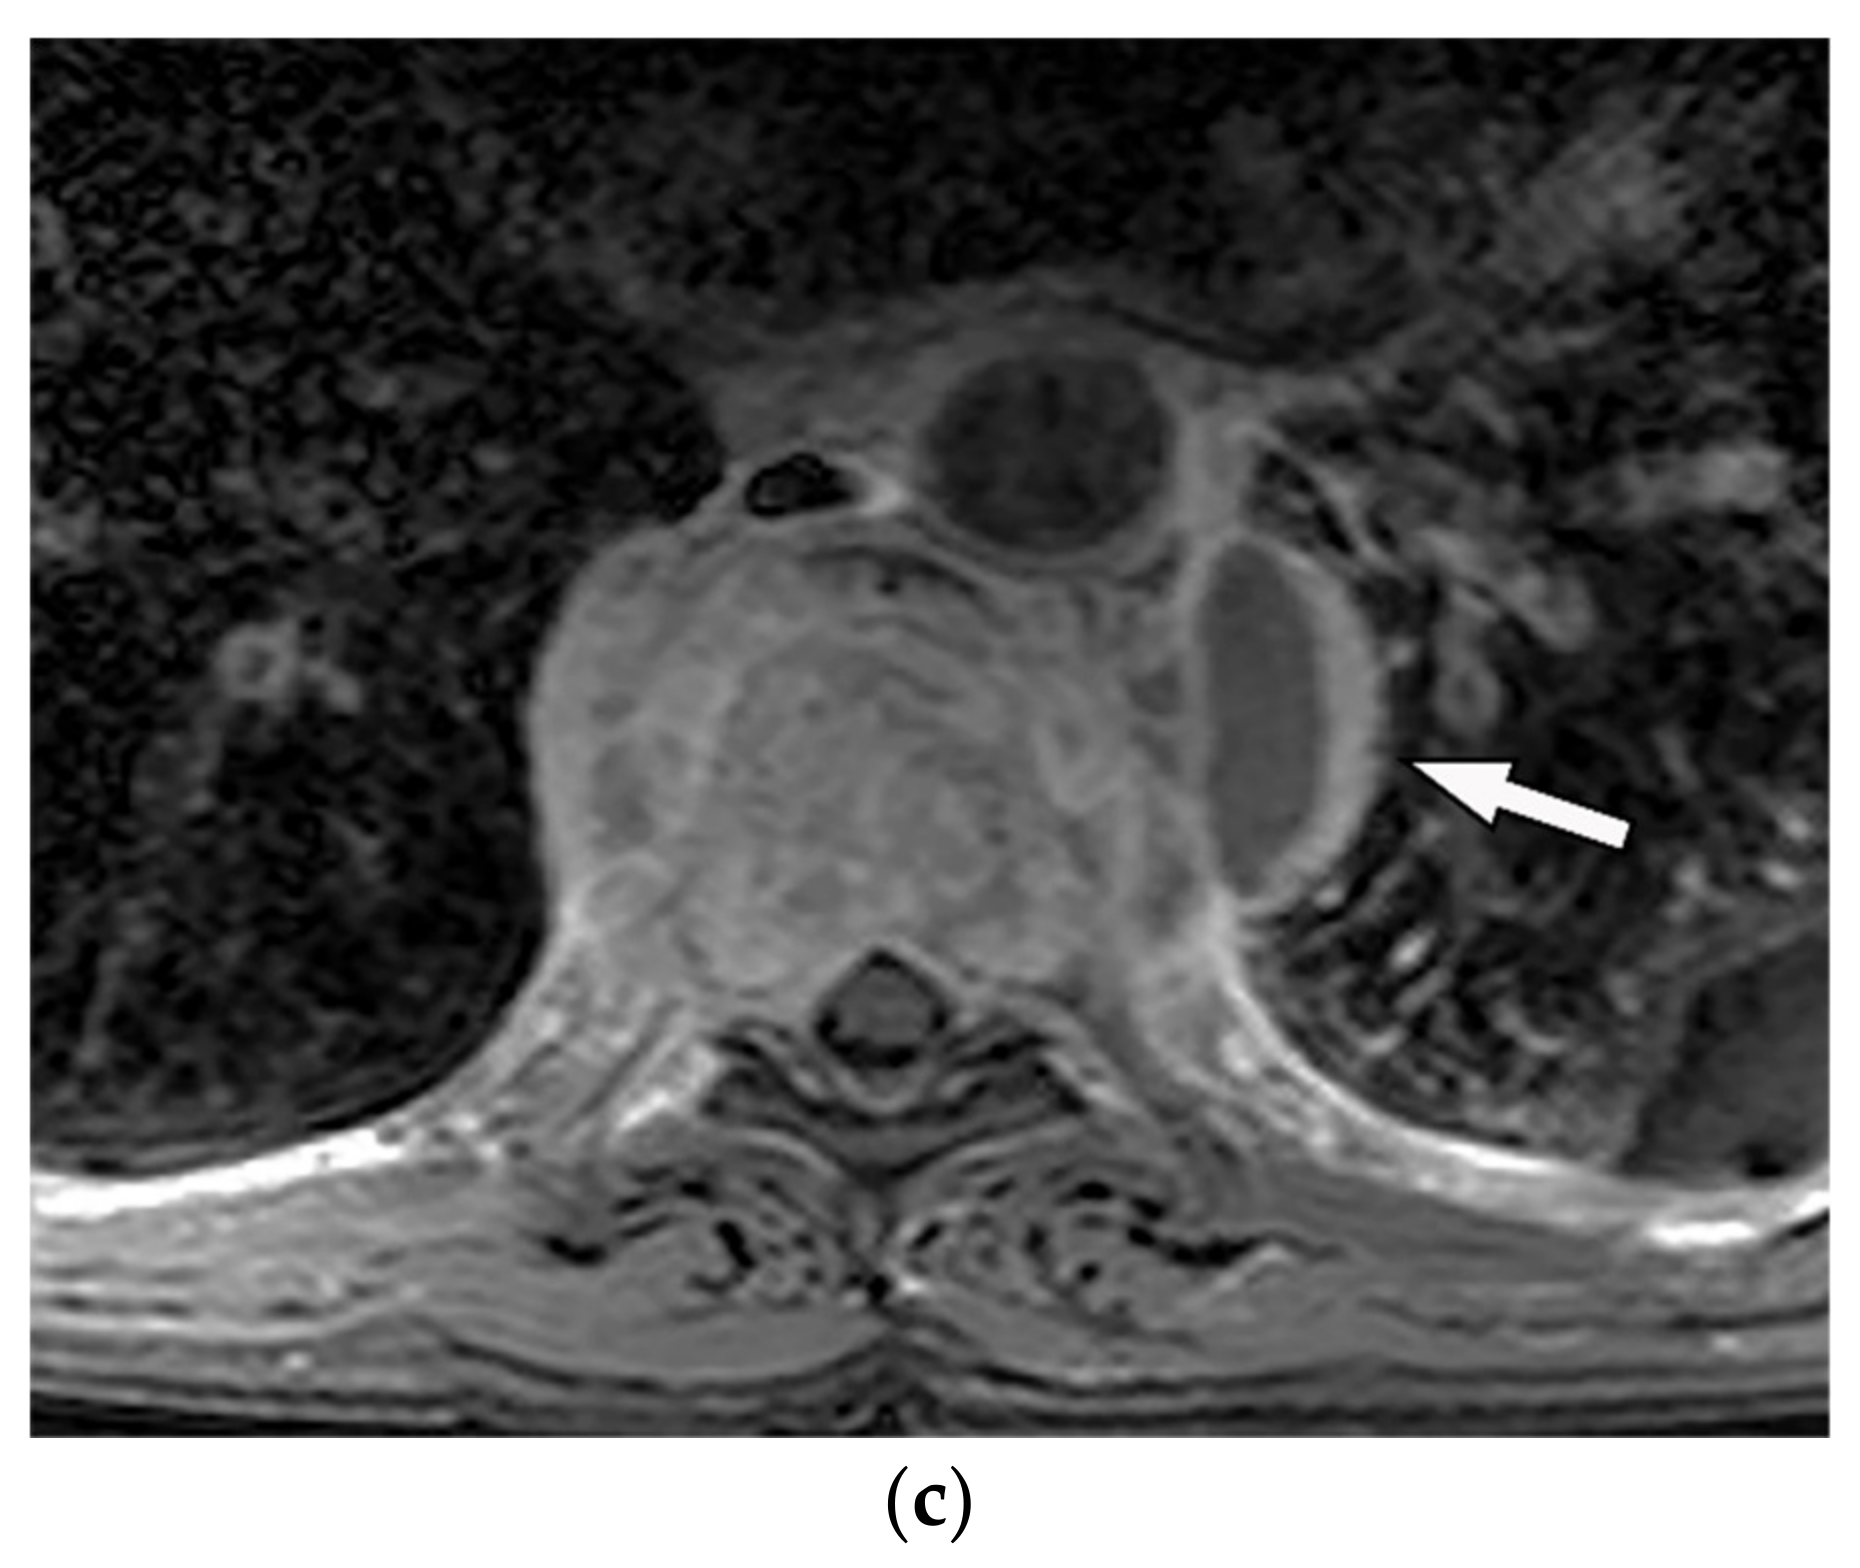

| Schwannoma | Well-defined mass with homogenous attenuation, “fat-split” sign, internal calcification in long-standing schwannomas, postcontrast enhancement except for areas of necrosis. | T1W: iso or slightly hyperintense; T2W: significantly hyperintense |

| Neurofibroma | Well-circumscribed mass with smooth margin and soft tissue attenuation, possible internal calcifications, rib erosion, neural foramina widening because of tumor extension along with the spinal nerve roots. | T2W, T1WFS + C: so-called “target sign” appearance: hyperintense rim and hypointense center |